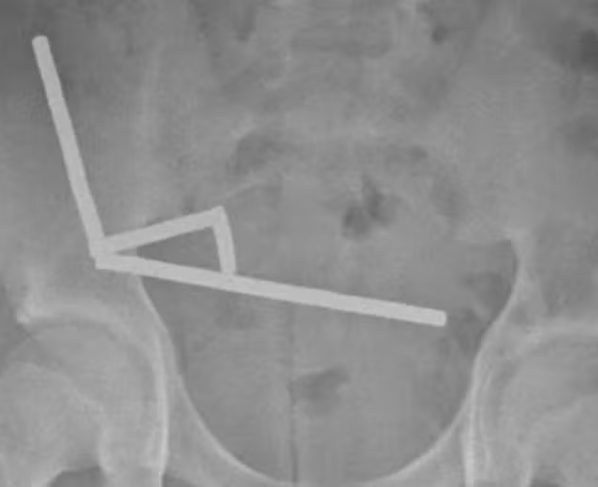

Os exames mostraram que os ímãs haviam se agrupado em quatro pontos distintos do abdômen, obrigando os médicos a realizar uma cirurgia de urgência. Parte do intestino delgado e grosso precisou ser removida. O menino permaneceu hospitalizado por oito dias até receber alta.